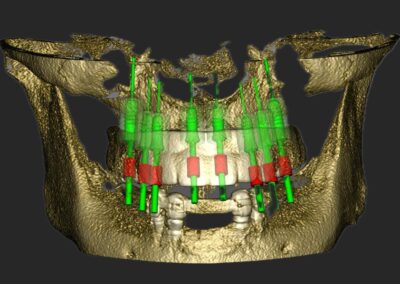

Bilder v.l.n.r.: 01 Herstellung der röntgenopaken Schablone zur Übertragung auf den Dicom-Datensatz / 02 Planung der Zahnimplantatstellung anhand der röntgenopaken Schablone / 03 Virtuelle Planung auf dem 3D-Modell / 04 Übertragung der Röntgenschablone auf dem Dicom-Datensatz (1:1) / 05 Virtuelle Plaung im Dicom-Datensatz / 06 Visualisierung frontal / 07 Visualisierung seitlich / 08 Visualisierung des Implantat-Falles frontal / 09 Visualisierung mit Bohrschablone

Ein entscheidender Bestandteil dieser modernen Praxis ist die Auswertung von 3D-Daten, die aus der Computertomographie extrahiert werden. Neuere Entwicklungen zeigen auch, dass Daten von optischen Scannern zunehmend in den Planungsprozess integriert werden. Diese umfassenden Informationen, kombiniert mit fortschrittlicher Implantatplanungssoftware, ermöglichen eine akkurate Simulation sowohl chirurgischer als auch prothetischer Phasen.

Vor der eigentlichen Operation können Implantatpositionen sorgfältig festgelegt werden, wobei spezifische Faktoren wie das Knochenvolumen und die -qualitäten, die Lage anatomischer Strukturen (wie Nerven, Gefäße und Nebenhöhlen), prothetische und ästhetische Bewertungen sowie präzise Messungen der Breite und Höhe des Knochens an den vorgesehenen Implantatstellen berücksichtigt werden. Auch die Abstände und Winkel zwischen den Implantaten lassen sich exakt berechnen, was entscheidend für den langfristigen Erfolg der Behandlung ist.

Ein weiterer Vorteil dieser Technologie ist die Möglichkeit der dreidimensionalen Positionierung der Implantate, die entscheidend für optimale klinische Ergebnisse ist, insbesondere in Bezug auf ästhetische Gesichtspunkte. Die geführte Implantatchirurgie (GIS) ermöglicht es, vorher geplante Rehabilitationsprojekte direkt und präzise in das chirurgische Feld zu übertragen. Dies fördert nicht nur die Genauigkeit, sondern kann auch dazu beitragen, eine minimal-traumatische oder lappenlose Operation durchzuführen.

3. Simulation und chirurgische Umsetzung

Moderne Planungssoftware erlaubt:

• Virtuelle Implantatinsertion

• Kollisionsanalysen

• Simulation augmentativer Maßnahmen

• Planung navigierter oder schablonengeführter Chirurgie

Die digitale Planung kann direkt in eine CAD/CAM-gestützte Bohrschablone überführt werden, wodurch die intraoperative Umsetzung hochpräzise erfolgt.